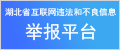

消融圖片

手術(shù)當(dāng)日,范群雄副主任醫(yī)師、趙繼先主任醫(yī)師領(lǐng)銜的手術(shù)團(tuán)隊嚴(yán)陣以待。此次手術(shù),穿刺環(huán)節(jié)是關(guān)鍵和難點。由于卵圓孔封堵器的存在,穿刺路徑受到了極大的限制。為了克服這一困難,手術(shù)團(tuán)隊采取了多項措施,確保手術(shù)安全、順利。首先,他們利用DSA(數(shù)字減影血管造影)和三維心臟建模技術(shù),對朱女士的心臟結(jié)構(gòu)進(jìn)行了精確的分析,使得手術(shù)團(tuán)隊能夠清晰地看到房間隔、卵圓孔封堵器以及周圍血管的位置關(guān)系,從而制定出更加精準(zhǔn)的穿刺路徑。其次,手術(shù)團(tuán)隊在穿刺過程中,小心翼翼地操控穿刺針,通過精準(zhǔn)把控力度和角度,在復(fù)雜的心臟結(jié)構(gòu)中準(zhǔn)確地找到穿刺點,并避免對周圍組織的損傷。

隨后,手術(shù)團(tuán)隊乘勝追擊,運用射頻消融技術(shù)進(jìn)行了雙側(cè)肺靜脈前庭及上腔靜脈電隔離,精準(zhǔn)地消除了房顫病灶,恢復(fù)了心臟的正常節(jié)律。緊接著,手術(shù)團(tuán)隊將左心耳封堵器放置到位,鉤掛穩(wěn)定。造影顯示,左心耳封堵完好,未見明顯殘余漏。這一步驟的成功,徹底阻斷了血栓形成的源頭,為朱女士的未來生活提供了有力的保障。